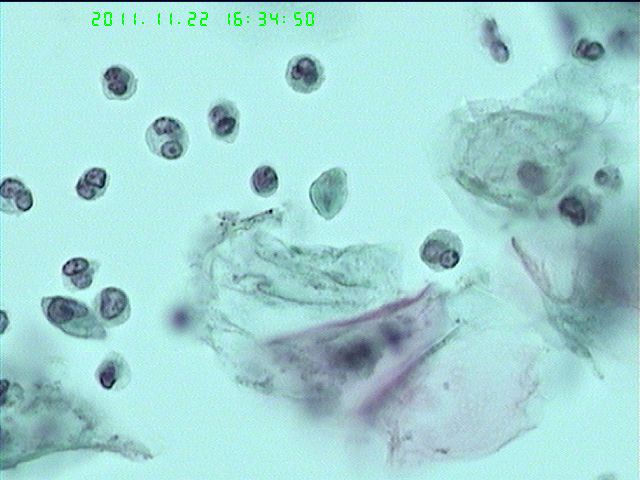

53岁宫颈液基

多数是中性粒细胞,中间是不是有滴虫?

像是滴虫,似有鞭毛。

滴虫

滴虫,5,12很典型

典型的滴虫,感染性背景,嗜双色细胞、空泡状像被虫子咬掉胞浆了的细胞(彭老师教的)